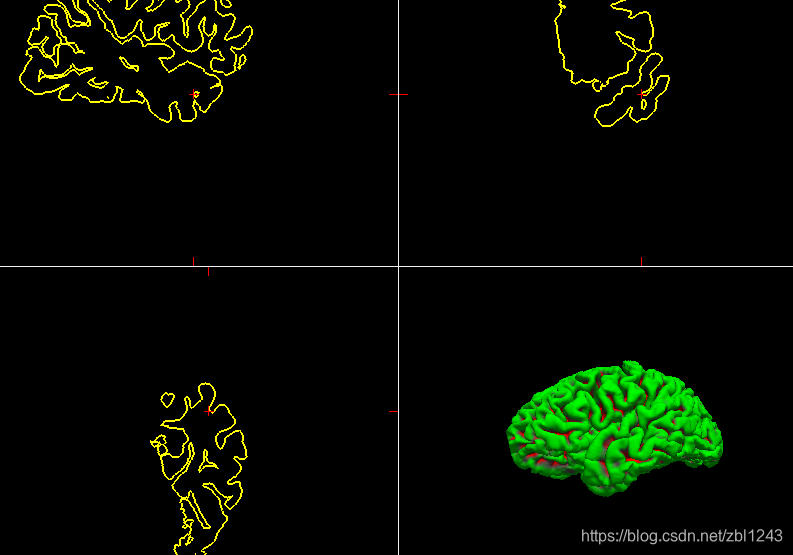

使用freesurfer查看一下,命令行:freeview,加开后加载surface,选择inflated:

lh.pial:

lh.white: